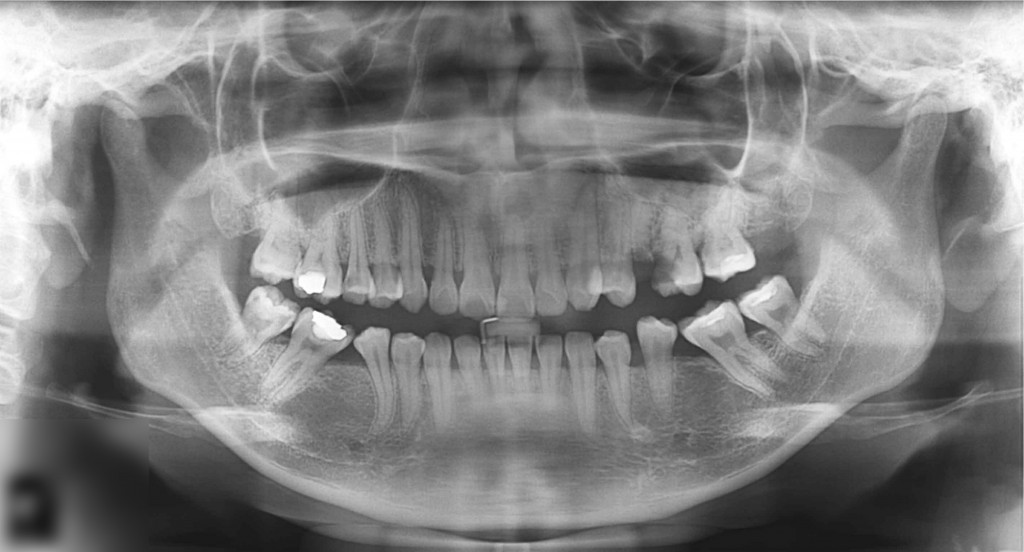

Planul de tratament recomandat a fost acceptat de pacient.

O nouă radiografie ne arată ameliorarea problemei inițiale. Tratamentele de canal au adus un aport substanțial la aceasta.